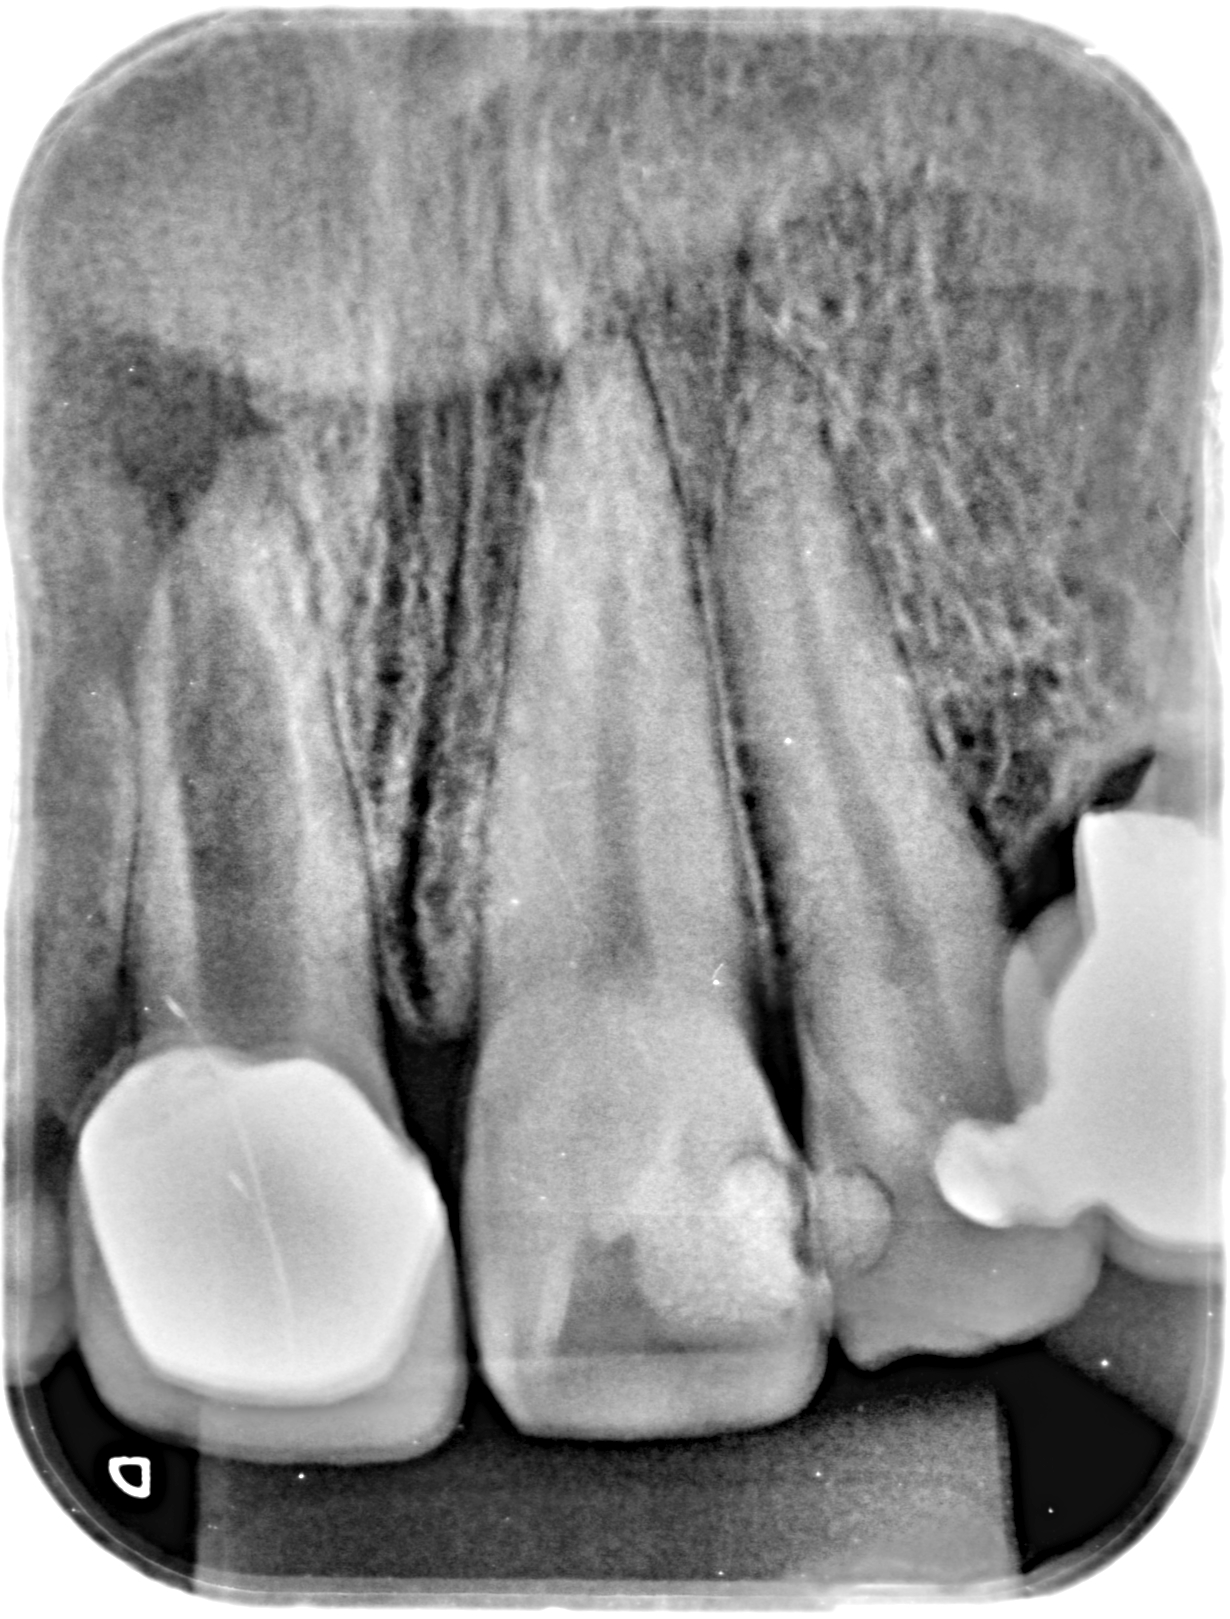

Panorámicas, periapicales y cefalométricas con sensores de última generación. Dosis mínima, máxima calidad.